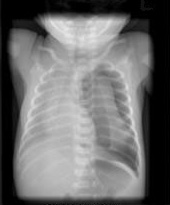

Bilden visar vänstersidig pneumothorax